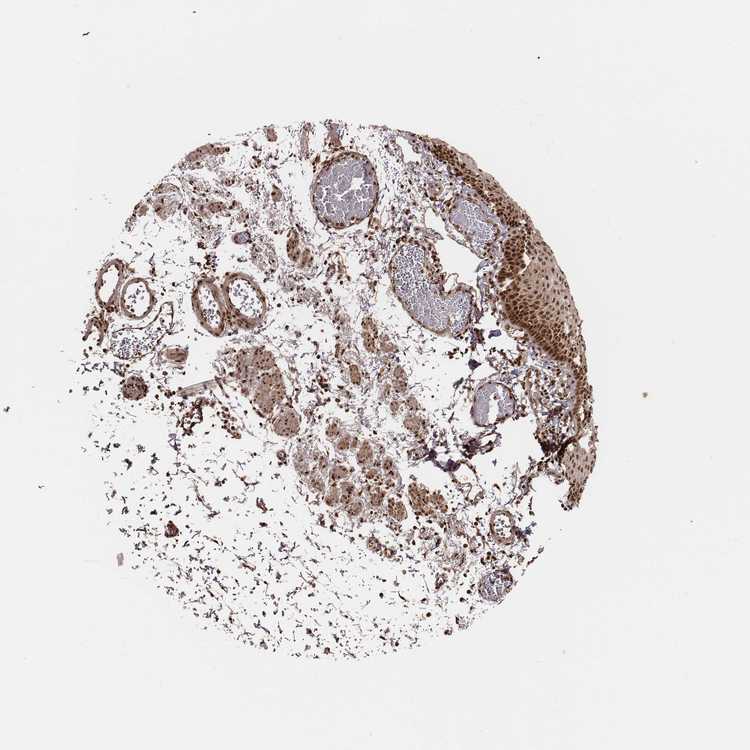

ESOPHAGUS - Antibody stainingi

Antibody staining in the annotated cell types in the current human tissue is reported as not detected, low, medium, or high, based on conventional immunohistochemistry profiling in selected tissues. This score is based on the combination of the staining intensity and fraction of stained cells.

Each image is clickable and will lead to virtual microscopy that enables deeper exploration of all samples and also displays staining intensity scores, fraction scores and subcellular localization as well as patient and tissue information for each sample.

Antibody HPA073519

Squamous epithelial cells High